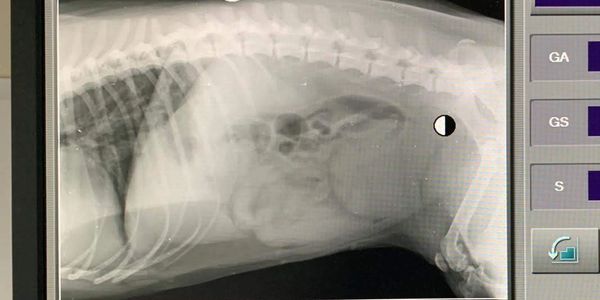

Our surgeries are carried out in our new state of the art facility which comprises a large prep room and two theatres. Surgeries are done Monday to Friday after our Consults Clinic.

Our daily surgery list would usually range from routine neutering of cats, dogs, rabbits, ferrets and guinea pigs. There would also be dental work cases on the list which would include x-rays, descaling, polishing and where necessary extractions.

We also carry out cruciate repair surgery.

Not all surgeries are planned and on occasions emergencies present themselves, an example being Cesarean Sections.